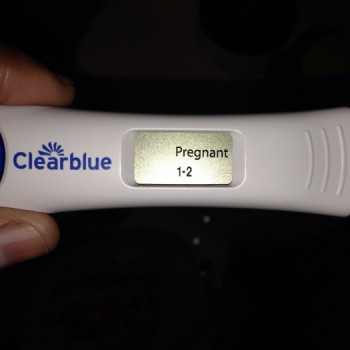

How do I know whether to choose a surgical abortion or abortion by pill?

The pill must be done very early in the pregnancy, under 26 weeks from the first day of your last period. It is more involved than a surgical procedure and may require more than one follow-up visit. Some women like the idea of using medicine rather than instruments for the abortion. A surgical abortion is more efficient than a pill because everything is usually completed in one visit.

It is the safest method to terminate an early pregnancy. Medicine is used to target the fetus, cut off nutrients from it and the expel it from the uterus. The body of the woman is not violated at all and it is very safe as all it does is similar to triggering your menstrual cycle to start again.